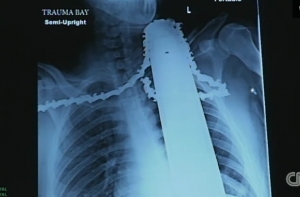

Опасный инцидент произошел с Джеймсом Валентайном в пригороде Питтсбурга. Мужчина работал цепной пилой на вершине сосны, когда неожиданно бензопила отскочила и режущей частью угодила в шею и плечо Джеймса. Коллеги мужчины смогли оперативно спустить пострадавшего на землю и отсоединить режущую часть от двигателя, но само лезвие с цепью трогать не стали, сообщает CNN в своем видеорепортаже.

Вскоре прибыли медики и отвезли мужчину в ближайшую больницу. Стоит отметить, что в это самое время мужчина находился в сознании. Медики сделали операцию, успешно извлекли пилу из тела и наложили мужчине три десятка швов. Оказалось, что лезвие повредило в основном мягкие ткани, на сантиметр не дойдя до сонной артерии. Сейчас молодой человек находится в стабильном состоянии с хорошим прогнозом на полное выздоровление.